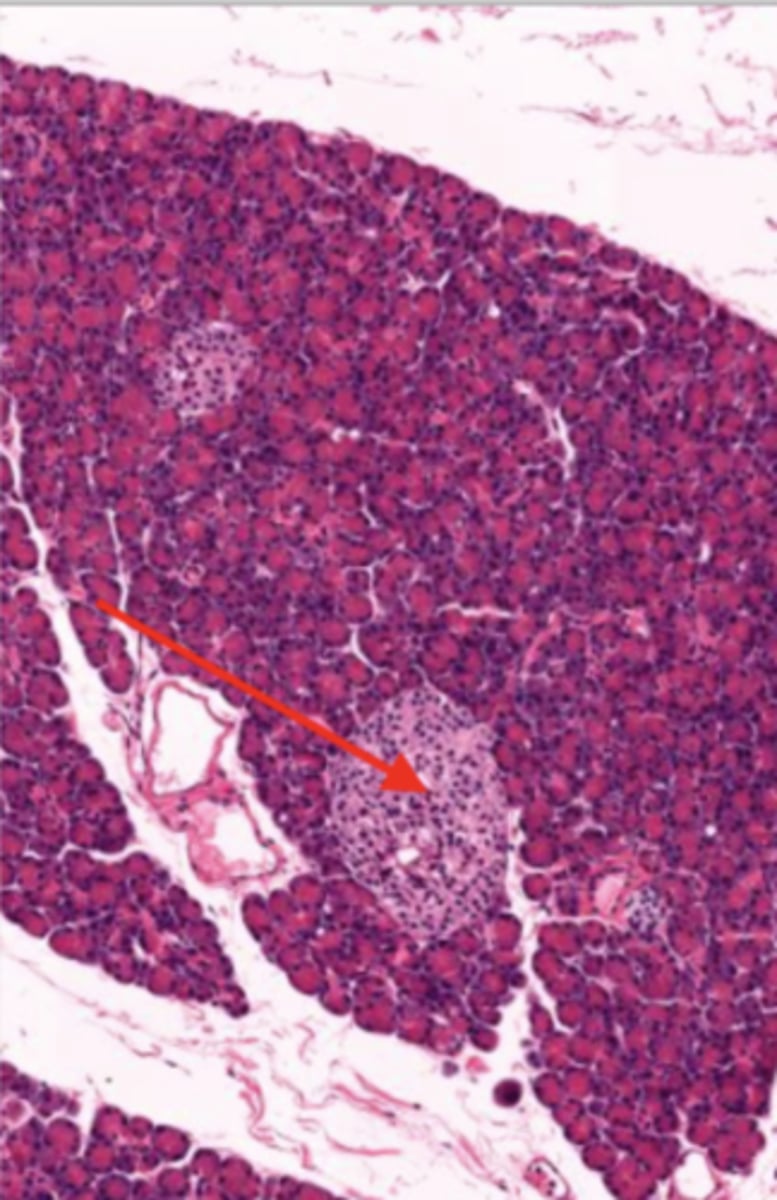

pancreas (histology)

islet of Langerhans (pancreas)

Acinar cells (pancreas)